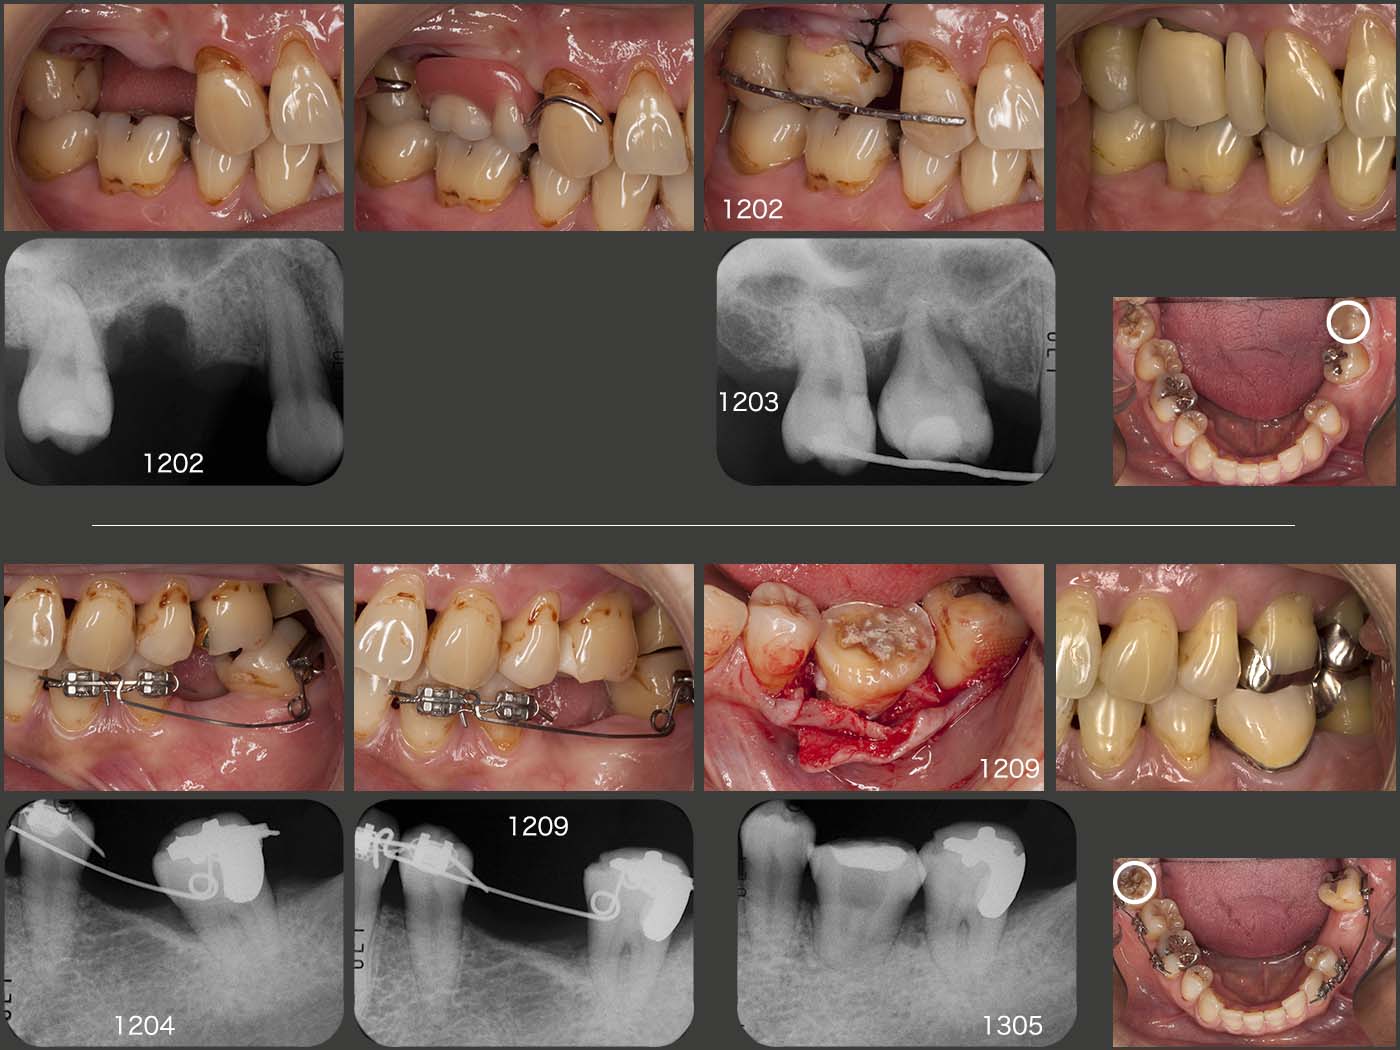

上段に右上の経過を示す.まず2012年1月,右上に暫間義歯を装着した.さすがに右上3のクラスプが審美的に好ましくないとのこと.そこで左下8を抜歯し,右上6の欠損部に移植した.(12年2月)

つぎに下段に左下の経過を示す.左下8をドナー歯として抜去したため,前方に傾斜していた左下7のアップライトが可能となった.こうして左下6部のスペースを拡大したのち,今度は右下8を左下6部に移植した.